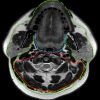

* Phân chia khoang vùng cổ: Vùng cổ được chia làm 2 phần trên và dưới dựa vào xương móng gồm vùng cổ trên móng và vùng cổ dưới móng. 3 lá mạc cổ sâu chia cổ thành nhiều khoang:

– Mạc cổ sâu, lá nông (SL-DCF: superficial layer, deep cervical fascia)

+ Cổ trên xương móng: vòng quanh khoang nhai và khoang mang tai; một phần bao cảnh

+ Cổ dưới xương móng: bao quanh cổ bởi các cơ treo, cơ ức đòn chũm và cơ thang.

– Mạc cổ sâu, lá giữa (ML-DCF: middle layer, deep cervical fascia)

+ Cổ trên xương móng (SHN): ML-DCF vạch rõ bờ sâu khoang niêm mạc hầu; góp vào bao cảnh.

+ Cổ dưới xương móng (IHN): bao quanh khoang tạng; một phần bao cảnh

– Mạc cổ sâu, lá sâu (DL-DCF: deep layer, deep cervical fascia)

+ SHN và IHN: bao quanh khoang cạnh cột sống

+ SHN và IHN: góp vào bao cảnh

+ SHN và IHN: mạc cánh là lá mỏng của DL-DCF tạo nên thành ngoài của khoang sau hầu và khoang nguy hiểm; cũng như thành sau khoang sau hầu tách từ khoang nguy hiểm.

* Cổ trên xương móng (SHN: suprahyoid neck): Các khoang từ nền sọ tới xương móng (ngoại trừ ổ mắt, các xoang và ổ miệng).

– Khoang bên hầu (PPS: parapharyngeal space).

– Khoang niêm mạc hầu/bề mặt niêm mạc hầu (PMS: pharyngeal mucosal space).

– Khoang nhai (MS: masticator space).

– Khoang cảnh (CS: carotid space).

– Khoang má (BS: buccal space).

– Khoang sau hầu (RPS: retropharyngeal space).

– Khoang quanh cột sống (PVS: perivertebral space).